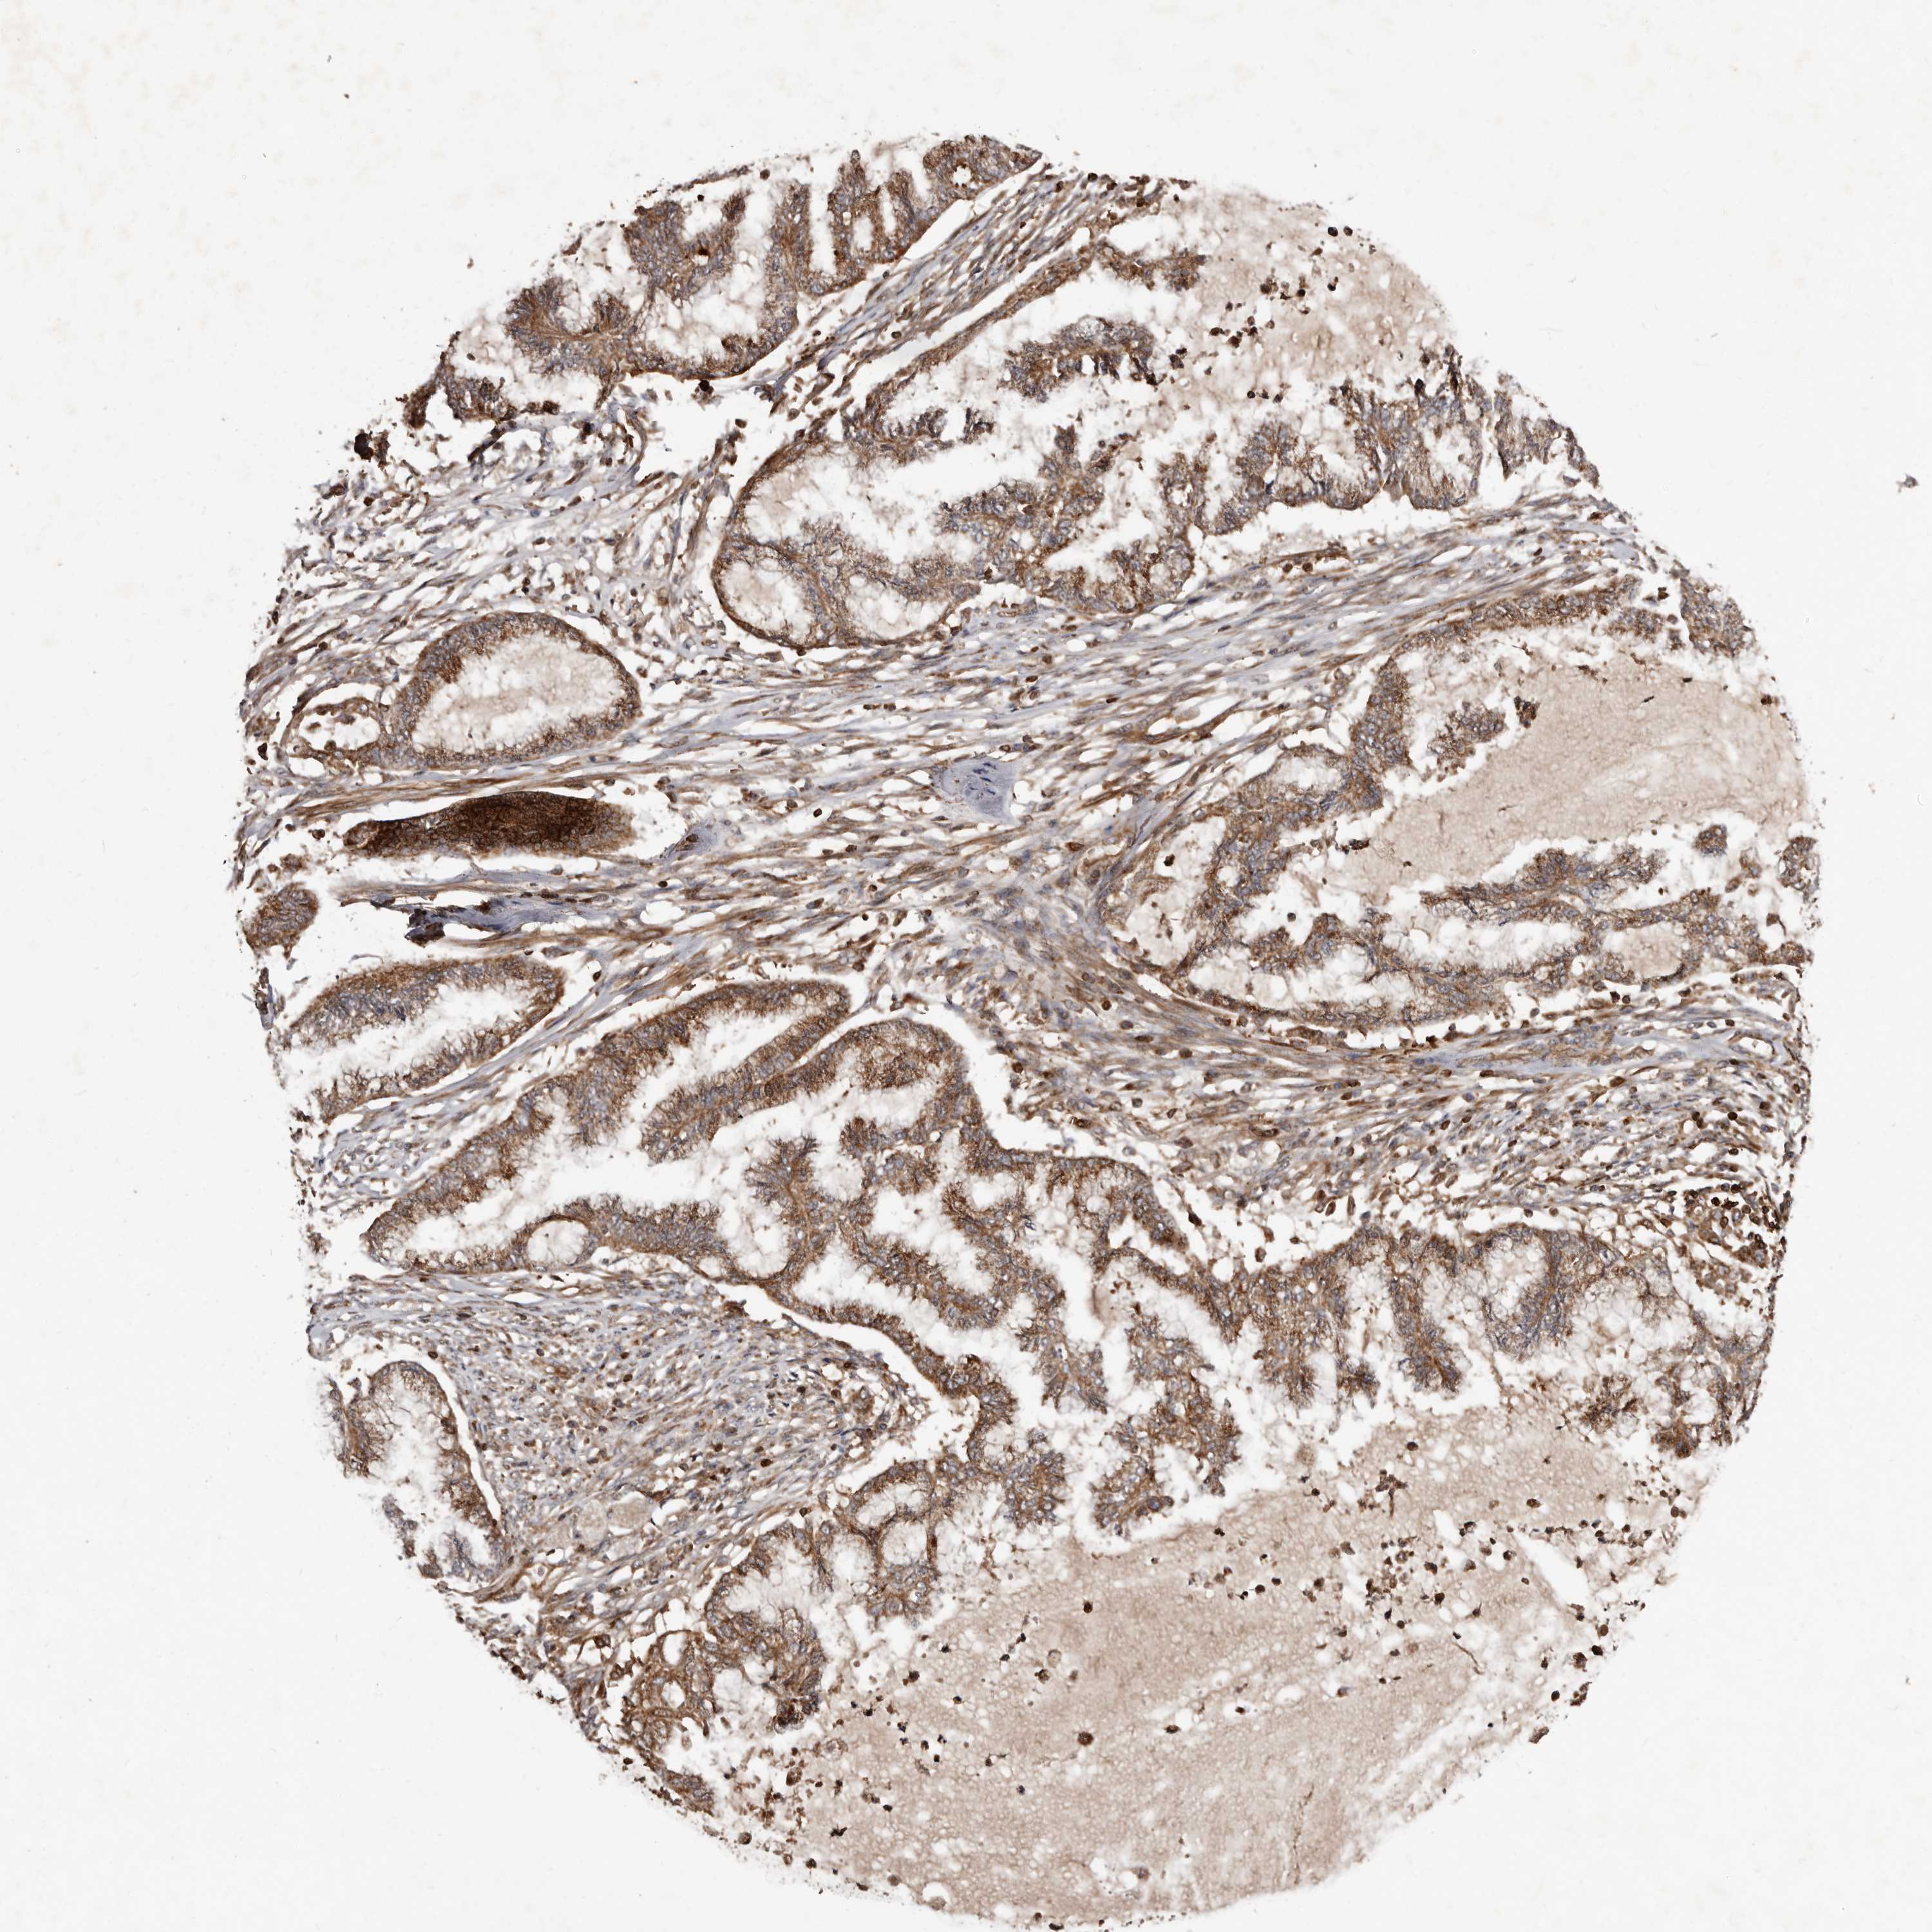

ENDOMETRIAL CANCER - Protein expressioni

A mouse-over function shows sample information and annotation data. Click on an image to view it in a full screen mode. Samples can be filtered based on level of antibody staining by selecting one or several of the following categories: high, medium, low and not detected. The assay and annotation is described here.

Note that samples used for immunohistochemistry by the Human Protein Atlas do not correspond to samples in the TCGA dataset.

Antibody stainingi

Antibody staining in the annotated cell types in the current human tissue is reported as not detected, low, medium, or high, based on conventional immunohistochemistry profiling in selected tissues. This score is based on the combination of the staining intensity and fraction of stained cells.

Each image is clickable and will lead to virtual microscopy that enables deeper exploration of all samples and also displays staining intensity scores, fraction scores and subcellular localization as well as patient and tissue information for each sample.

Antibody HPA027878

Antibody CAB004206

Staining

High

Medium

Low

Not detected

Intensity

Strong

Moderate

Weak

Negative

Quantity

>75%

75%-25%

<25%

None

Location

Nuclear

Cytoplasmic/membranous

Cytoplasmic/membranous,nuclear

Adenocarcinoma, NOS

Adenocarcinoma, metastatic, NOS

Neoplasm, malignant, NOS